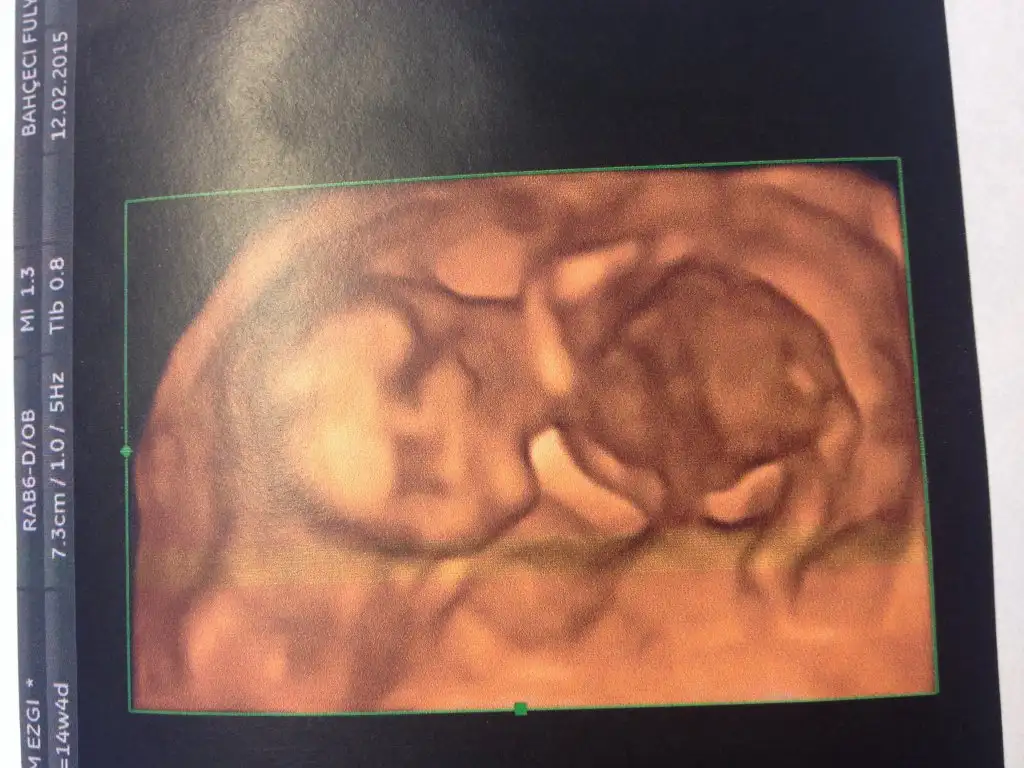

Ben de kontrolden geldim. Bu doktorumuz da kesin erkek dedi. 3 boyutlu gördük bugün. Bütün mal meydandaydı:) Resmen boks yapar gibiydi. 1 dakika durmadı, kıpır kıpır. Artık boy ölçülmeyecekmiş. Kilosu ölçülecekmiş. 114gr olmuş Ali Bey.

Oyy kuzum.. Allah nazarlardab saklasin.. maşallah maşallah..Eki Görüntüle 1412205